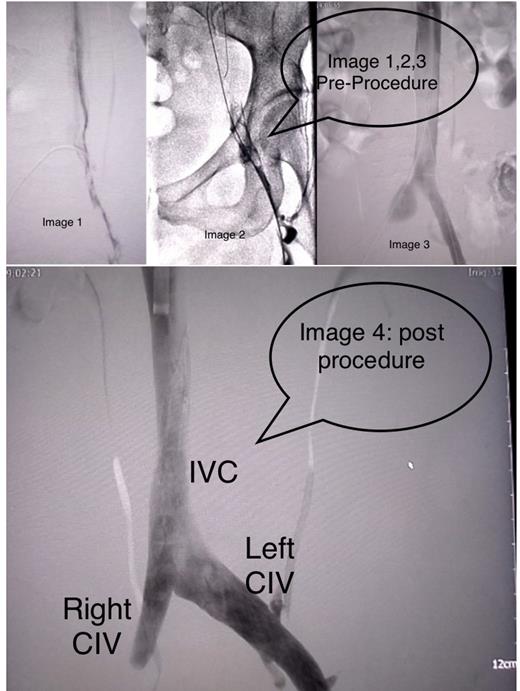

Invasive Radiology was consulted and she had a venogram and intravascular ultrasound (IVUS) which showed high-grade right common iliac vein and IVC stenosis (>90%) at L4 superior endplate. Iliac stenting and angioplasty improved iliac and inferior IVC diameters. Patient also underwent thrombectomy & IVC filter placement. The diagnostic venography revealed a popliteal-to-proximal femoral vein rethrombosis. This was treated with tissue plasminogen activator (TPA) by 8 French power pulse AngioJet and a mechanical thrombectomy. This resulted in partial clearing of the common femoral vein with persistent narrowing and thrombosis of the popliteal vein. TPA was infused at 1 mg/hour with a 5 French McNamara lysis catheter over the popliteal region.Patient transferred to ICU for overnight intravenous thrombolysis.

Ultrasound imaging typically cannot detect the high pelvic abnormalities seen in MTS. Contrast venography, MRI, or IVUS are needed to diagnose MTS 4. As was the case in our patient, venography should be done to evaluate stenosis and iliac vein compression hemodynamics after thrombus removal.